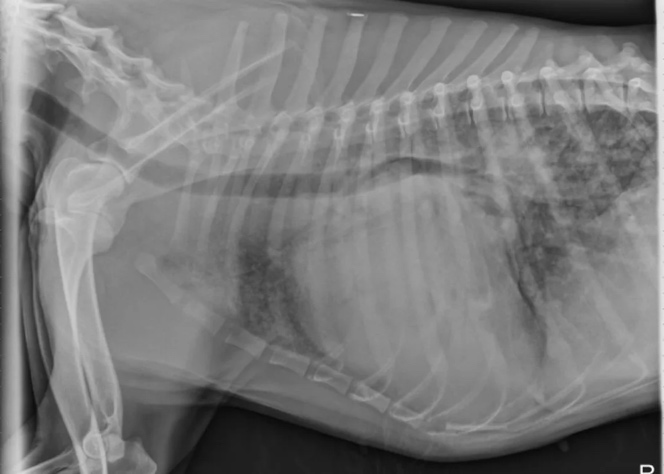

• A 10-year-old Giant Schnauzer is presented to you for unretractable coughing, restlessness and exercise intolerance. On examination, the dog is afebrile but markedly panting, mucous membranes appear pink. On auscultation, you note a prominent grade III-IV/VI left apical systolic murmur and a gallop. Auscultation of the lungs reveals bilateral harsh sounds. A bounding pulse is palpable over the femoral artery. You take thoracic radiographs. Which medication is most appropriate given the above diagnosis?

high dose furosemide, ramipril and possible pimobendan

• Ramipril is an ACE inhibitor that helps to reduce blood pressure and improve blood flow to the heart.

• Pimobendan = positive inotrope and vasodilator